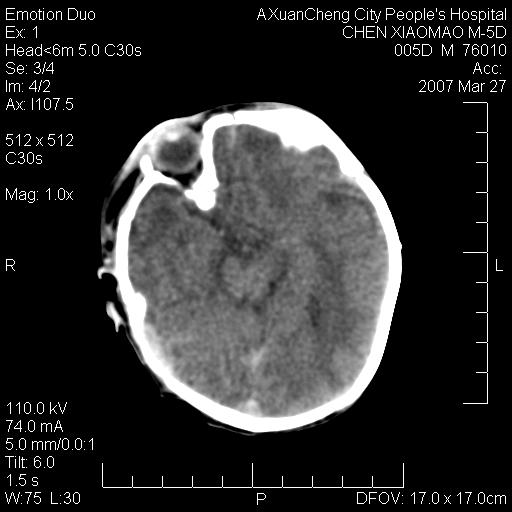

大家看看可有出血?另外枕骨中央是骨缝还是骨折

缝是正常的,但患儿有hie

大家看看可有hie ?还有左侧枕部胡形高密度ct为45~53hu,可有硬膜下血肿?

左颞枕部有出血,枕骨有骨折

未见明显异常,,那是横窦影,“缝”是后囟